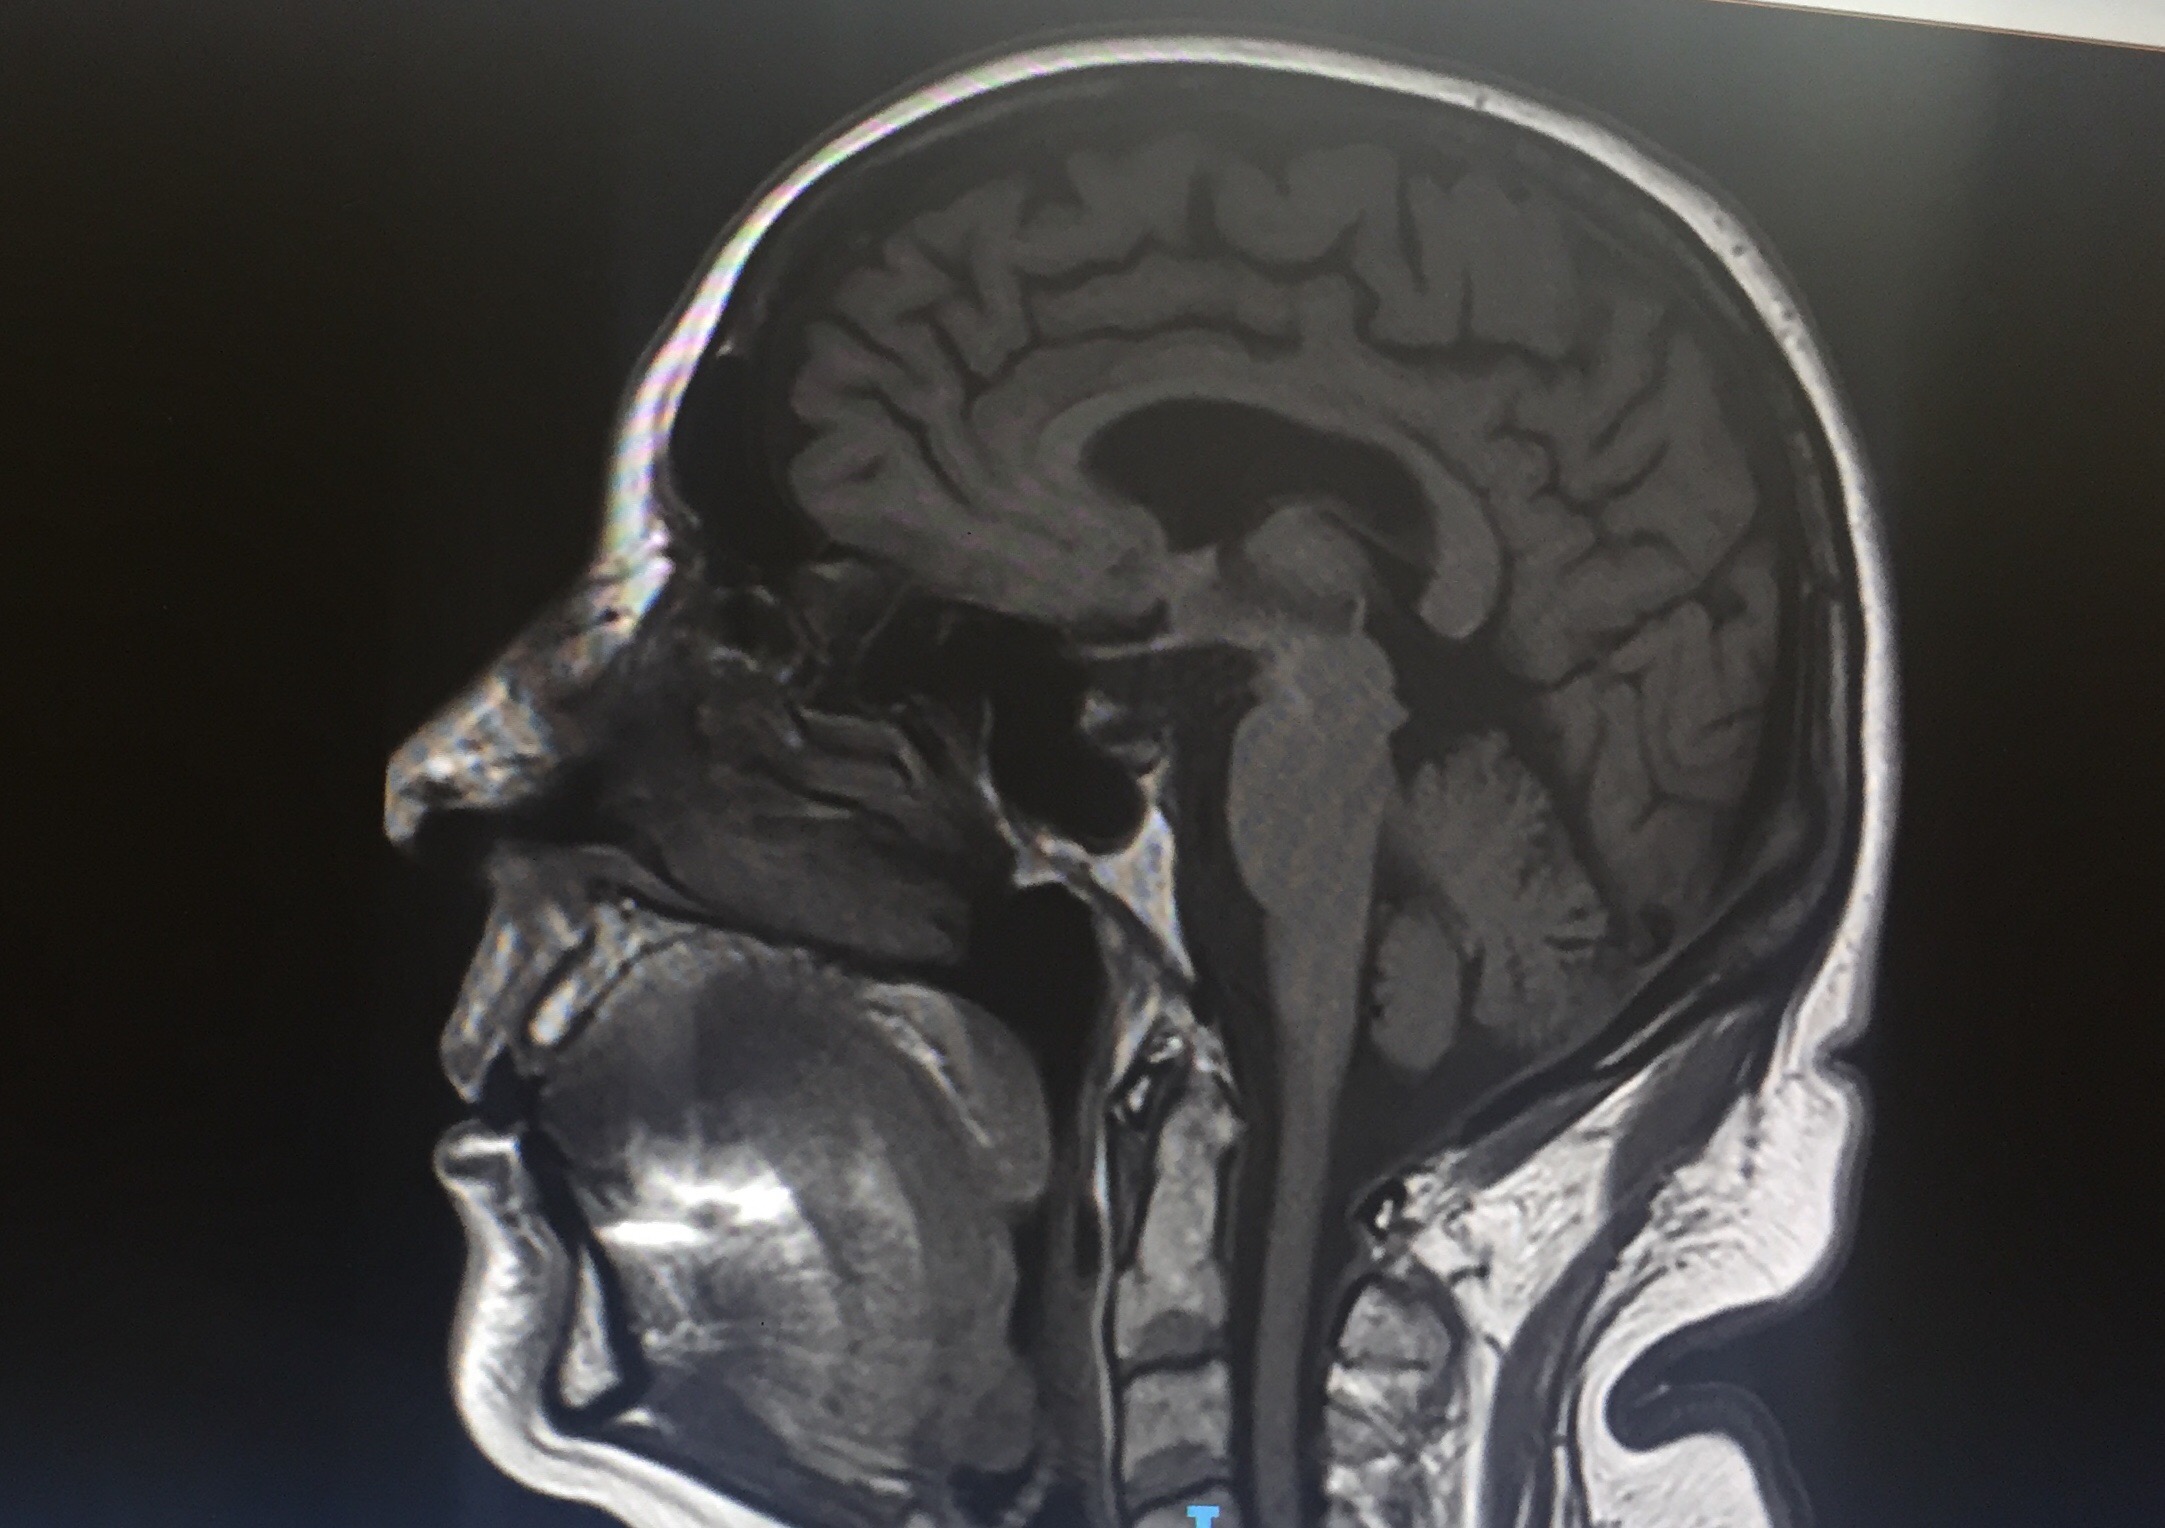

Graeme, my physio went onto his computer and showed me the results from the MRI I had at Flinders, and the Pet scan I had at the Royal Adelaide Hospital.

He read me the notes that were attached to each photo from the MRI and the Pet Scan, and I was able to photograph the MRI and the Pet Scan from the screen onto my iPhone.

Graeme was also able to tell me that my stroke had affected the right side of my body, because of the symptoms I had described to him.

These are the external evidences of my stroke, and who knows what are the internal effects of the stroke within my brain.

The information from the MRI and the Pet scan, does not give the doctors any clues as to what caused my stroke.

So the doctors are no wiser now than they were before I had the MRI and the Pet scan about the cause of the stoke.

It is only my reporting that I “feel” different and my description of those differences that is evidence of my having had a stroke.

Time alone will tell whether my brain will regenerate itself and the effects of the stroke will diminish over time.